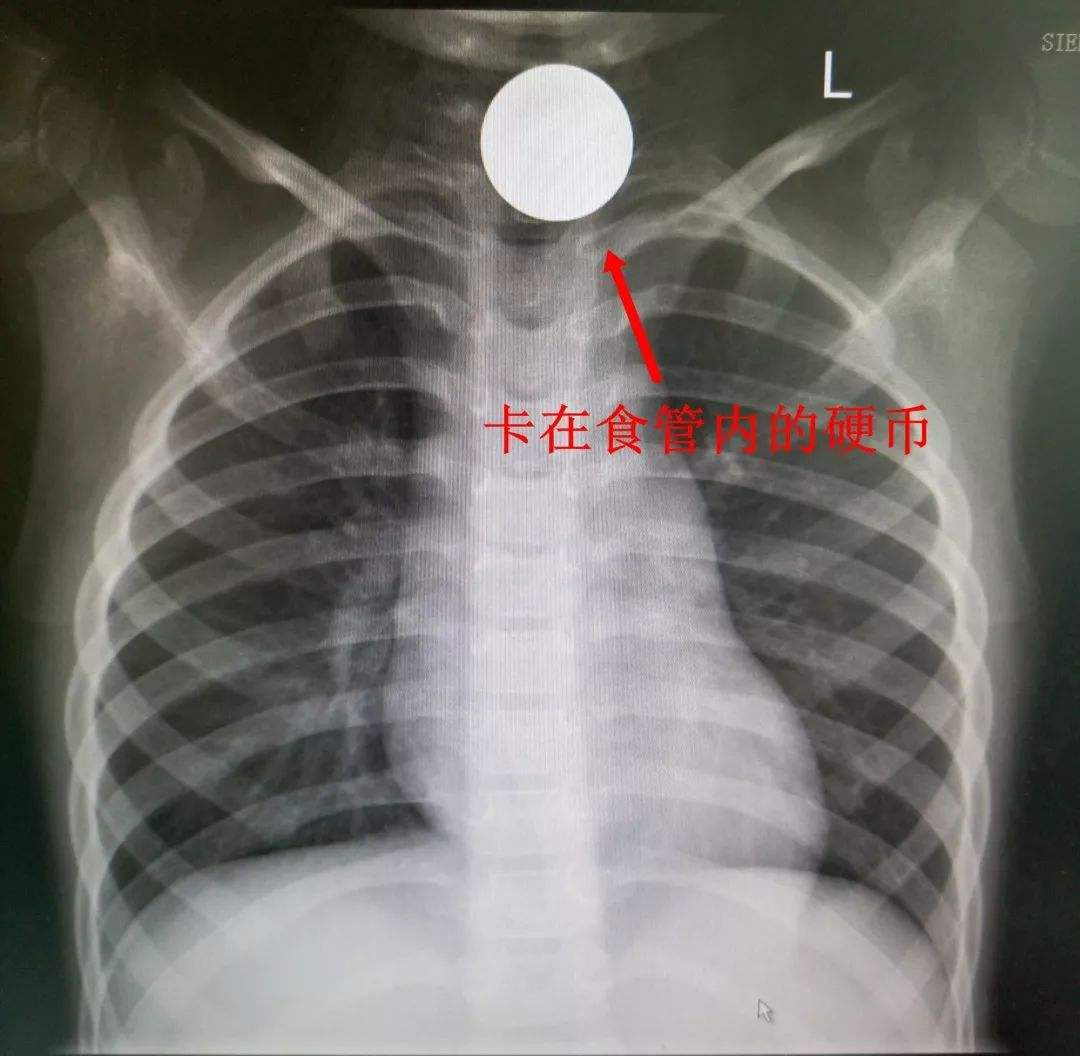

云县人民医院消化科 : 警惕食道异物谨防“祸”从口入

【2020-04-13】 浏览量:540